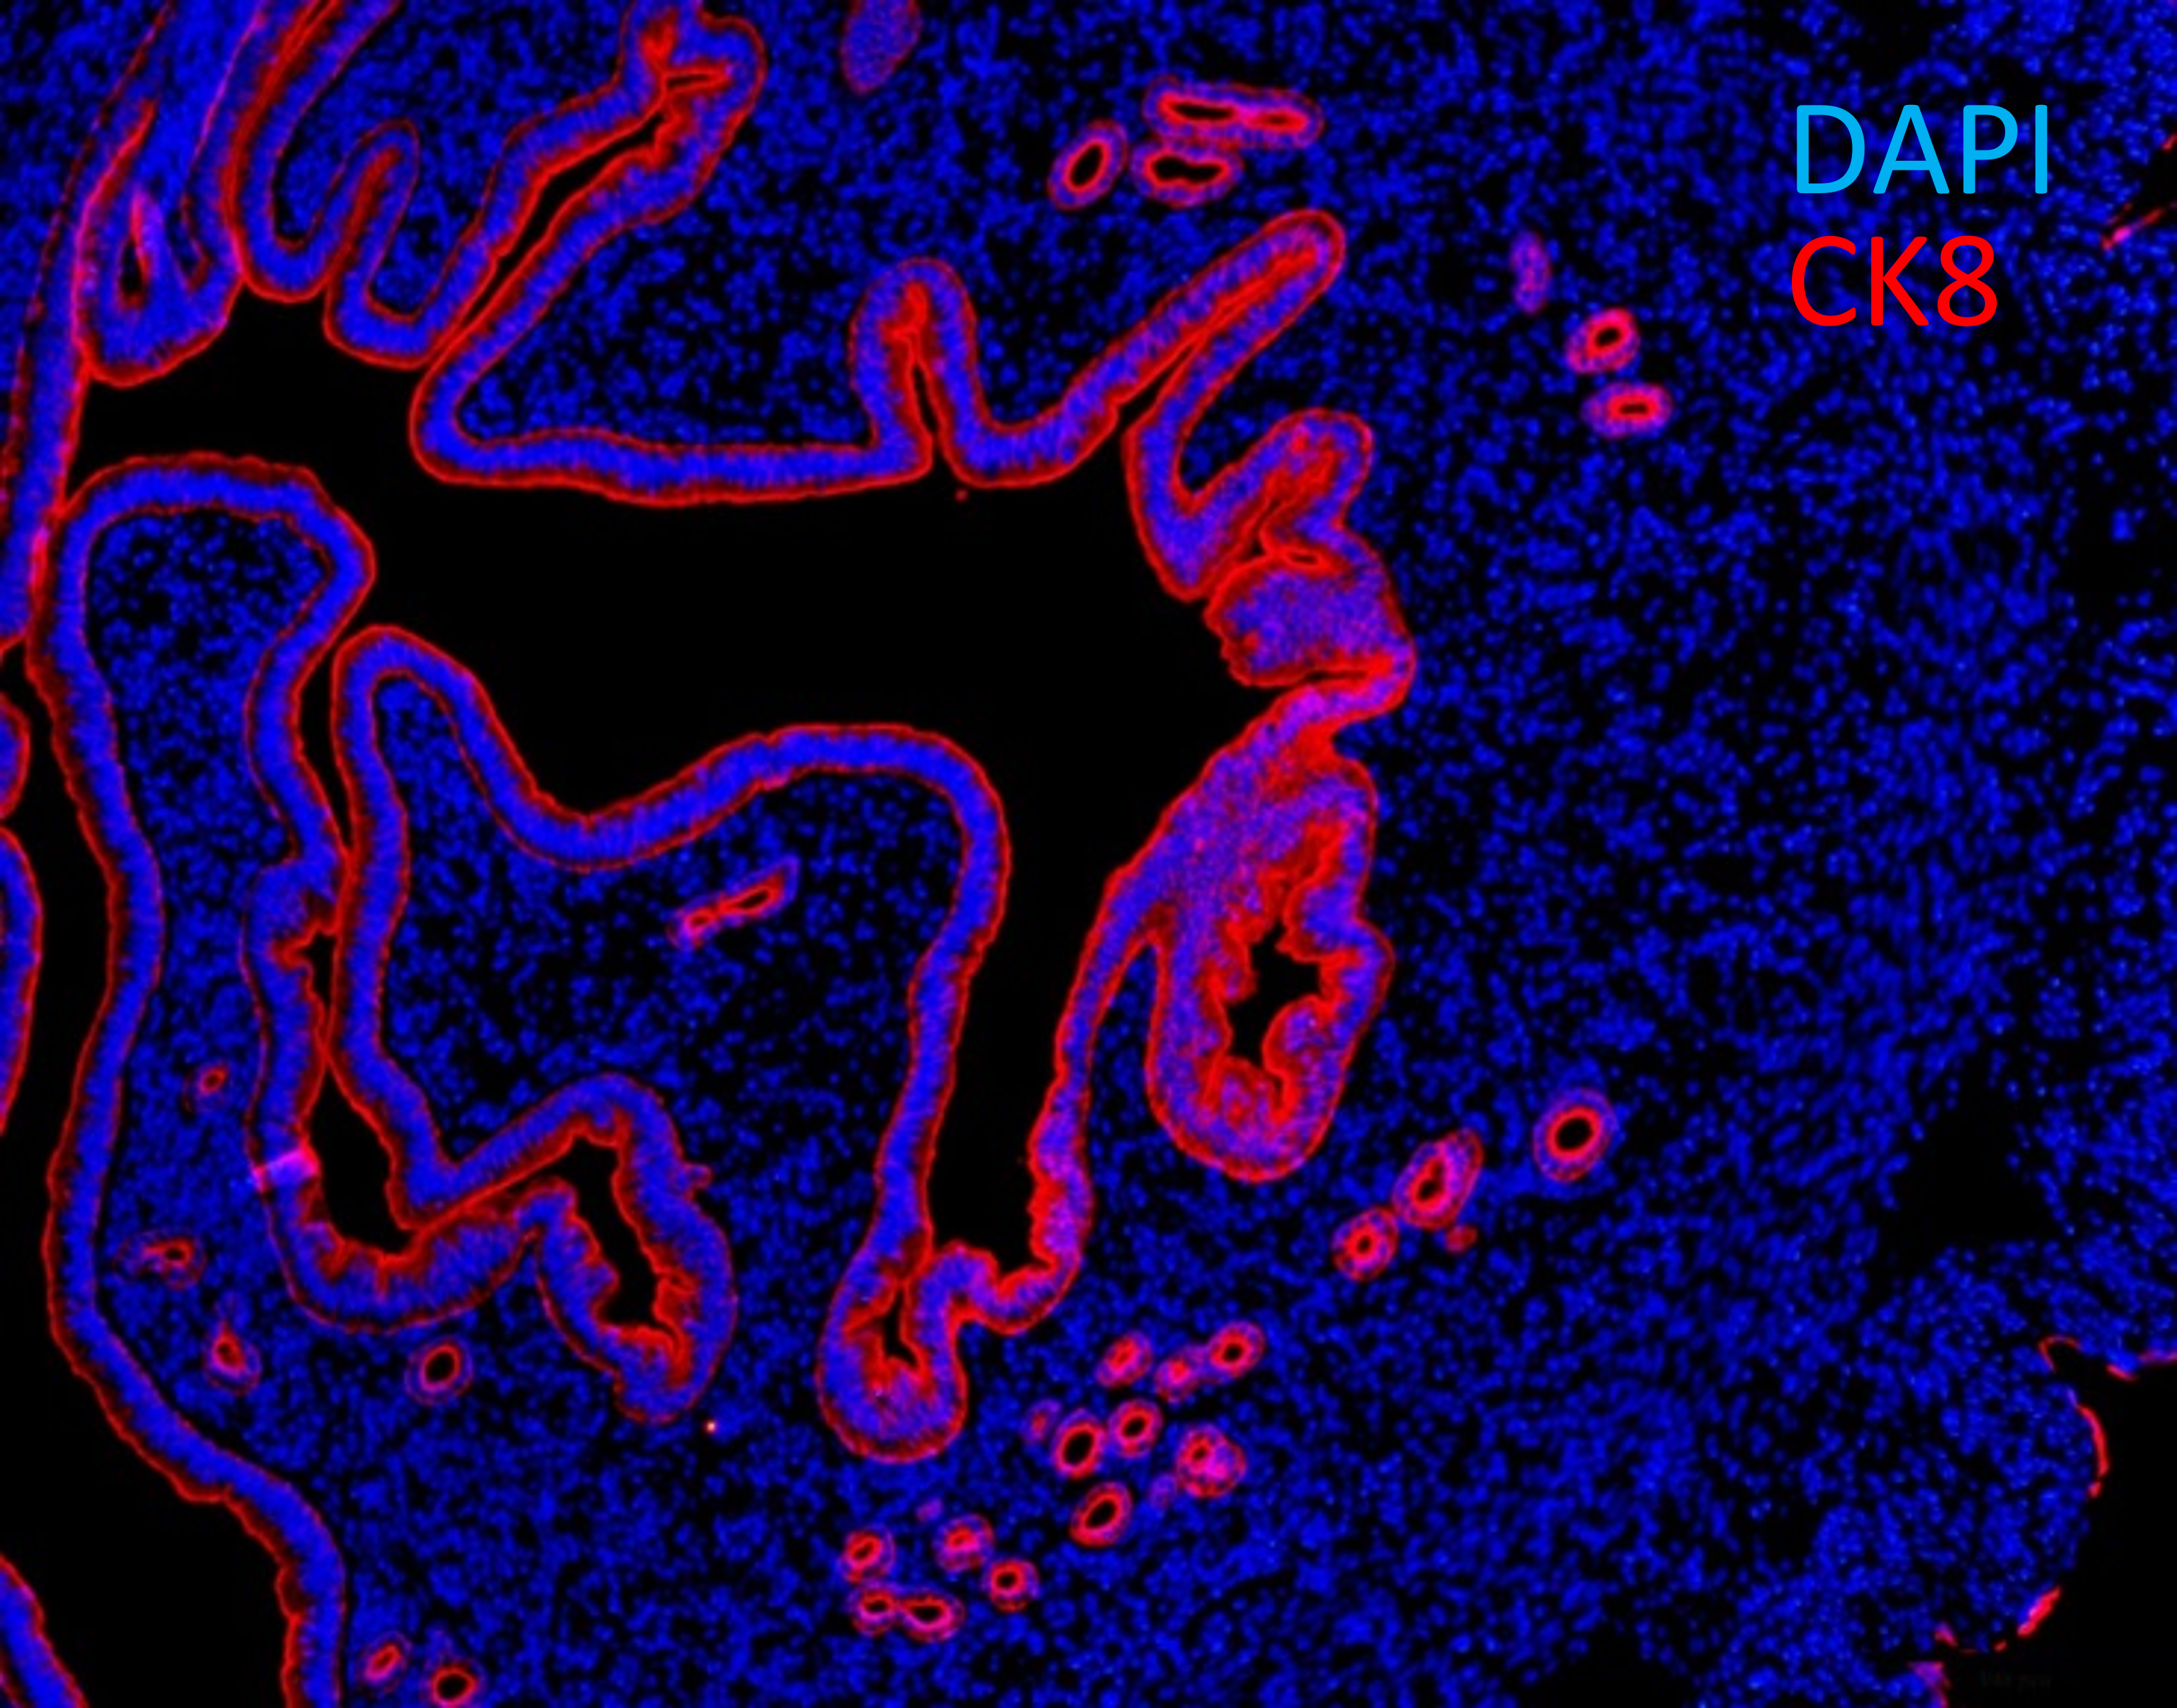

Embryo-uterine interactions

Main topic of our study in this field is the process of embryo implantation. The implantation process is an attachment of an embryo to the uterus wall. We approach this issue by modeling embryo implantation in vitro. We are particularly interested in tissue engineering and in 3D constructs (group of models in which cells reside in 3D scaffold) as a substrate for in vitro implantation. Currently we've been developing such model that can mimic some aspects of the embryo-endometrium interaction. In our model we use epithelial and stromal cells isolated from mouse endometrium.

Fig. 10. Cross-section of murine uterus with endometrial epithelial cells expressing cytokeratin 8 (CK8, red).

We are also planning to study early postimplantation development of mouse embryo using our implantation model. For the implantation, response of luminal epithelium to the hormonal and embryo-derived signals is crucial. To develop 3D equivalent of mouse endometrium we are also trying to understand mechanisms of functioning of endometrial epithelial and stromal cells as well as their interactions and responses to hormones using 2D cultures of epithelial and stromal cells isolated from mouse endometrium.

And last but not least of our research topics is to locate and describe the elusive population of endometrial stem/progenitor cells. This population is responsible for cyclical regeneration of endometrium and presumably plays role in diseases such as endometriosis and endometrial cancer.